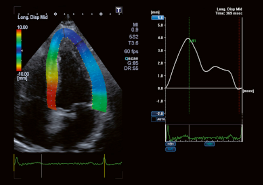

Wall Motion Tracking (WMT) позволяет зафиксировать и проанализировать движение стенок миокарда. WMT отслеживает деформацию миокарда и смещение его участков (спекл-трекинг). Технология может быть использована как в 2D, так и в 3D режимах. Спеклы - это изменения ультразвука отражателями в ультразвуковом пучкеnd ™..Toshiba делает акцент на большой роли стандартизации параметров деформации миокарда и активно поддерживает Объединенную рабочую группу Американского общества эхокардиографии (ASE) и Европейской ассоциации Эхокардиографии (EAE). Анализ WMT может выполняться как в онлайн, так и в автономном режиме на основе файлов DICOM, содержащих необработанные клипы с данными, отправленные на рабочую станцию. WMT незаменим для диагностики ишемических повреждений миокарда и определения точной локализации инфаркта.

Технология 2D Wall Motion Tracking - проводит сегментарный анализ (16 или 17 сегментов по ASE) миокарда для вычисления циркулярной, радиальной и продольной деформации;

Пример кривой смещения стенки левого желудочка на основе шести сегментов.

Для определения начального контура полости левого желудочка необходимо выбрать три точки в конце диастолы.

Кроме оценки деформации миокарда в 2D WMT режиме можно оценить следующие объемы:

• КДО - конечный диастолический объем

• КСО - конечный систолический объем

• ФВ - Фракция выброса

• ММЛЖ - масса миокарда левого желудочка

• Кривая объема

• Кривая массы левого желудочка